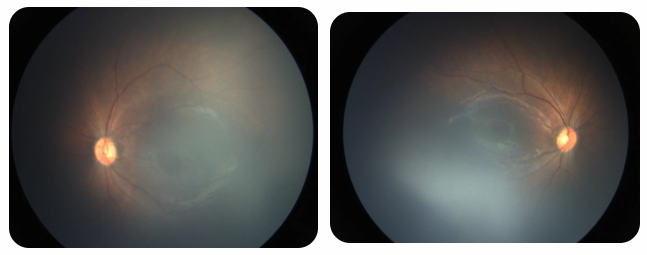

廈門眼科中心黎曉新名醫(yī)工作室曾接診一名31周出生的早產(chǎn)兒,出生體重僅1300克。由于家長缺乏篩查意識,直到孩子5個月大時眼睛仍不會追光,才前來就診。檢查發(fā)現(xiàn),患兒ROP已進展至4B期,因纖維血管增殖牽拉導(dǎo)致視網(wǎng)膜脫離,錯過了最佳治療窗口。盡管黎曉新教授團隊成功實施了玻璃體切割手術(shù),孩子的視力仍存在不可逆損傷。此后,孩子開啟了長期隨診復(fù)查、治療的“護眼征程”,目前其右眼矯正視力為0.6,左眼為0.8。

近期術(shù)前檢查:

早產(chǎn)兒視網(wǎng)膜病變

術(shù)后復(fù)查:

相比之下,另一位早產(chǎn)寶寶在出生5周后,生命體征穩(wěn)定之時,便在產(chǎn)科醫(yī)生的建議下轉(zhuǎn)診至廈門眼科中心。經(jīng)篩查確診為Ⅲ期ROP,黎曉新教授團隊及時為其進行了激光治療。半年后復(fù)查顯示,寶寶的視網(wǎng)膜血管發(fā)育正常,視力發(fā)育與足月兒童無異。